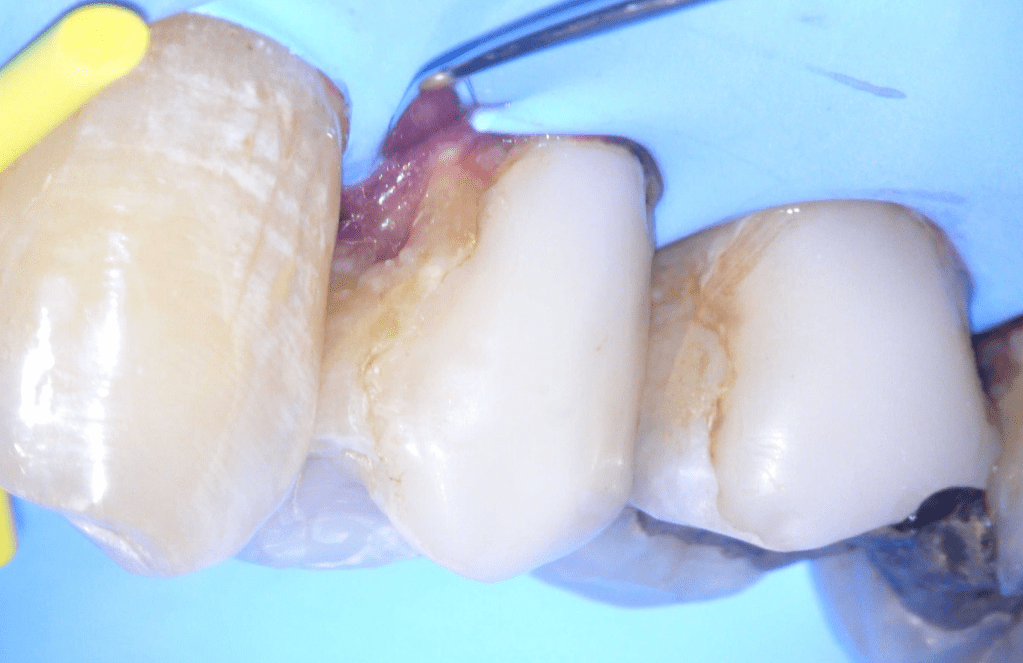

Reconstrucción preendodóntica

Reco pared vesticular

Reco pre-endo gingivectomái, pared yuxtaosea

Reco preendo + gingivectomía